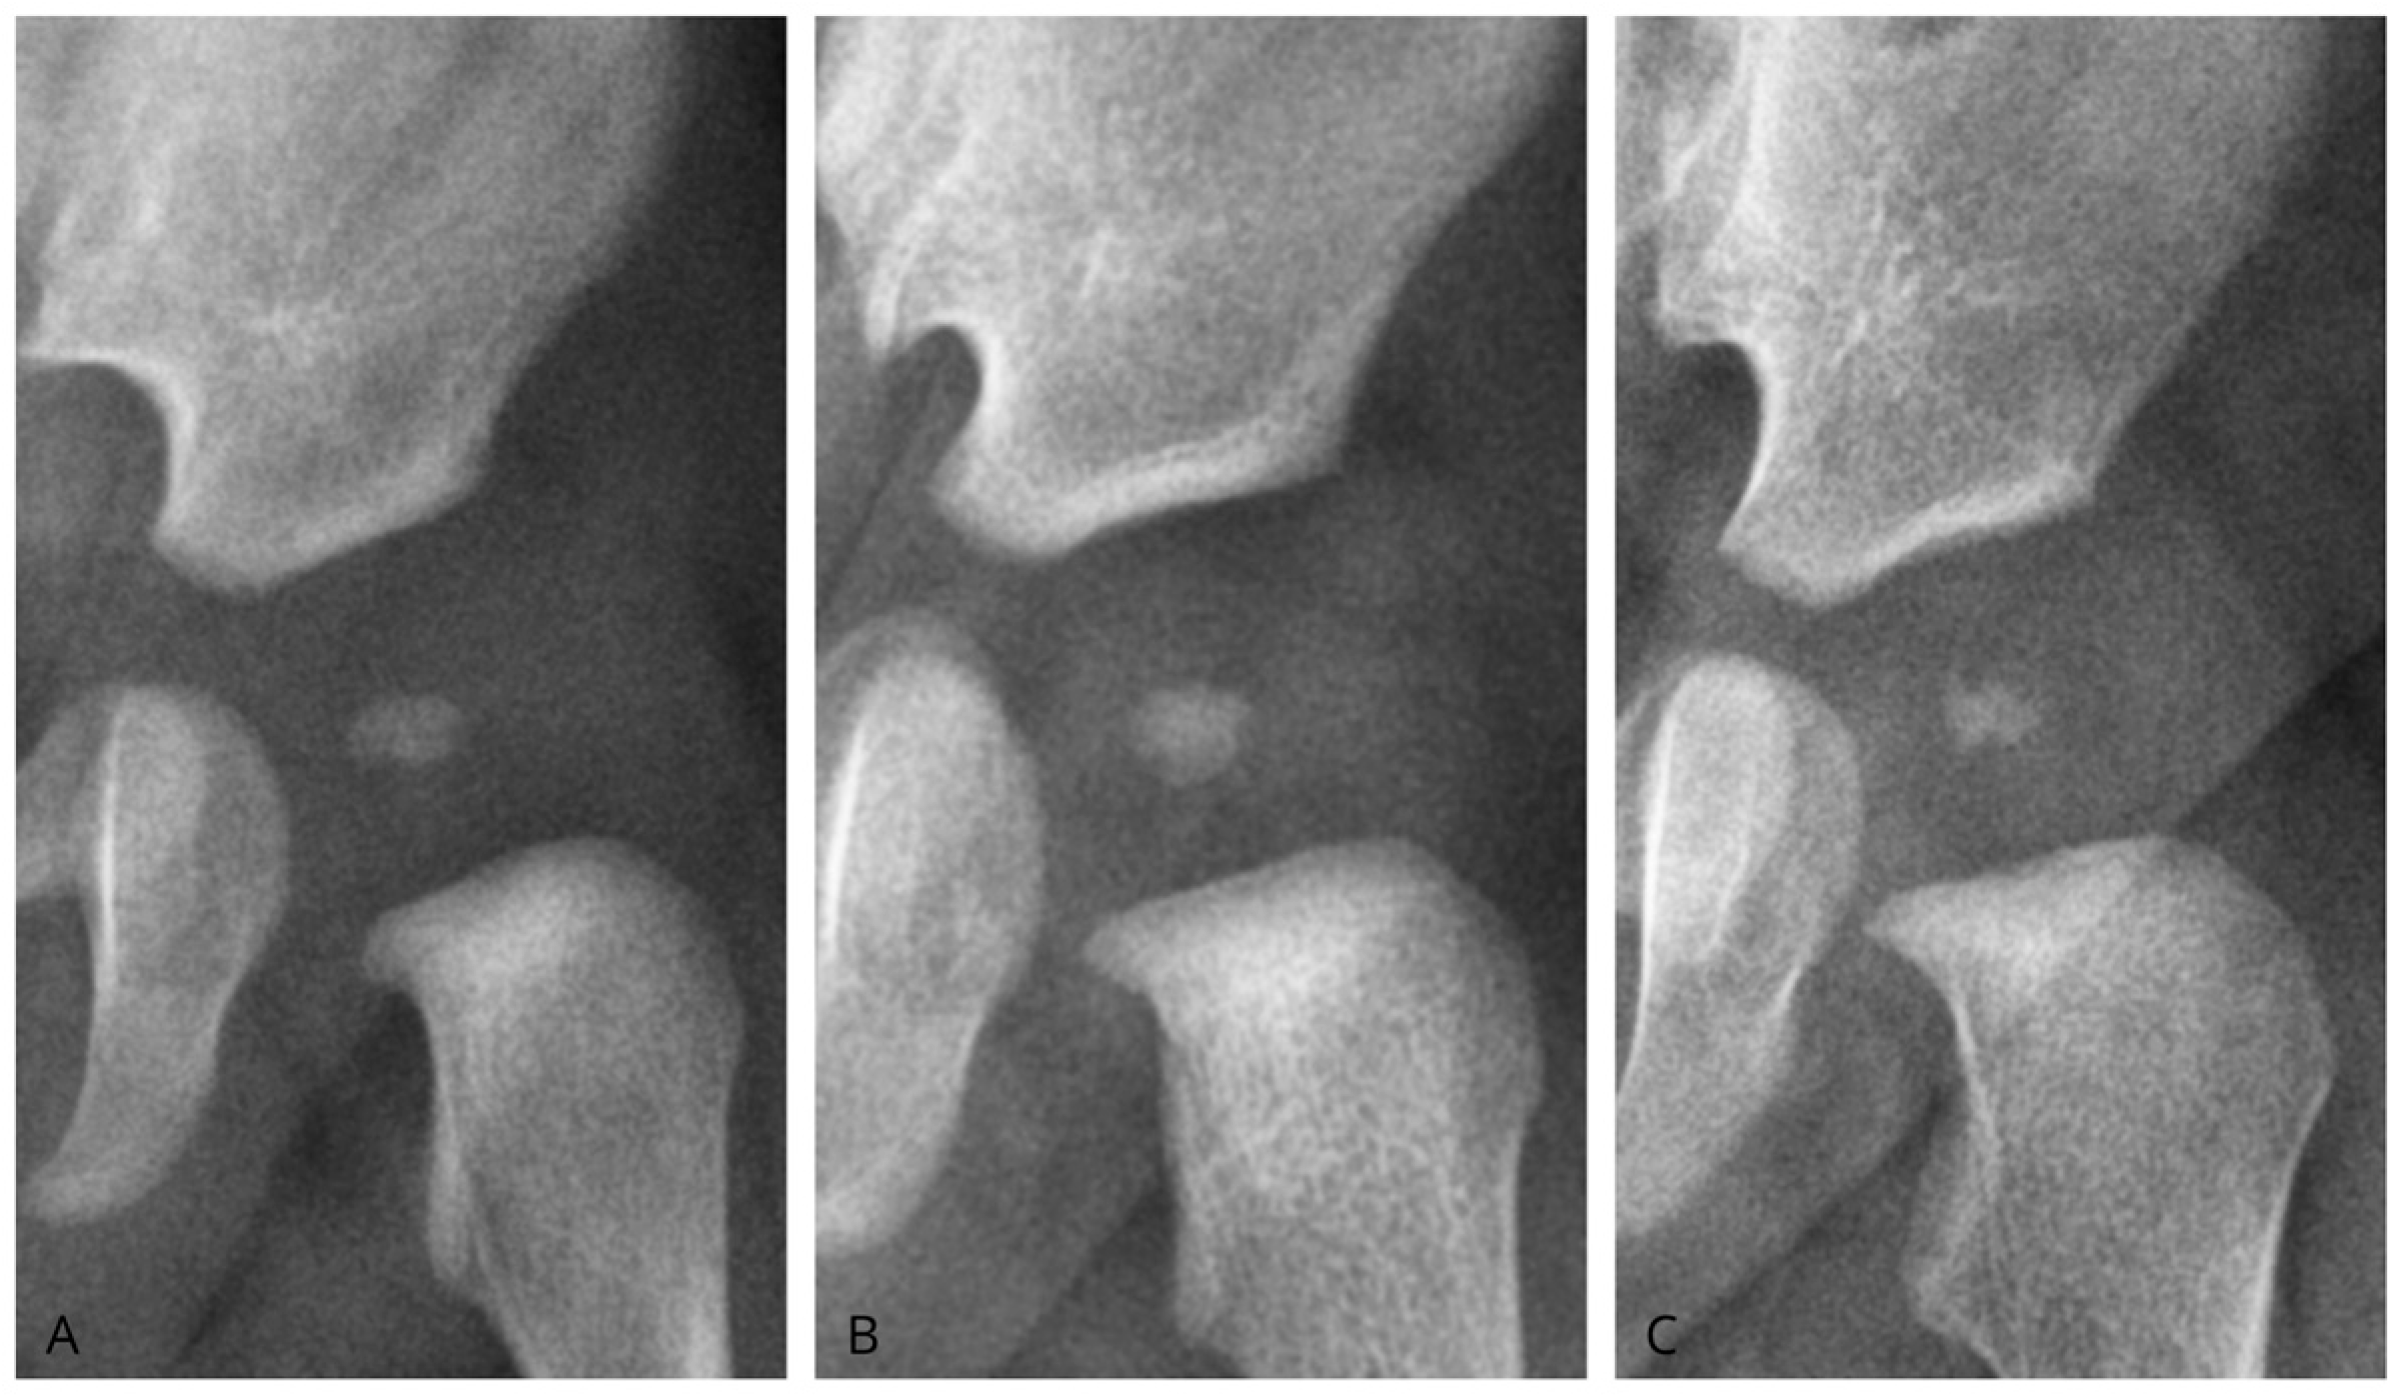

We classified ONFH morphology as oval, round, or irregular (Figure 3). Oval nuclei had transverse dimensions exceeding longitudinal dimensions with homogeneous density. Round nuclei showed equal axes (±10%) with homogeneous density. Irregular nuclei displayed asymmetrical axes or uneven contours and heterogeneous density. To assess the reliability of the measurements, Cohen’s kappa coefficient was calculated to determine the strength of agreement among the different morphologies analyzed.

Figure 3. Morphology of the femoral head ossification nucleus. (A): Nucleus classified as oval; (B): Nucleus classified as round; (C): Nucleus classified as irregular.